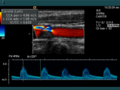

Die Aussagekraft der Sonografie kann erheblich durch die Anwendung des Doppler-Effekts erhöht werden. Man unterscheidet eindimensionale Verfahren (Pulsed-Wave-Doppler, Continuous-Wave-Doppler, auch als D-mode bezeichnet) von zweidimensionalen, farbkodierten Anwendungen (Farbdoppler – F-mode). Die Kombination B-Bild mit Pulsed-Wave-Doppler (PW-Doppler) nennt man auch Duplex.[4]

Doppler-Verfahren werden benutzt zur Bestimmung von Blutfluss-Geschwindigkeiten, zur Entdeckung und Beurteilung von Herz(klappen)fehlern, Verengungen (Stenosen), Verschlüssen oder Kurzschlussverbindungen (Shunts).

Dagegen kann man beim Pulsed-Wave-Doppler (PW-Doppler) für eine ortsselektive Geschwindigkeitsmessung im konventionellen B-Mode das sogenannte Gate festlegen. Es wird dann nur die Geschwindigkeit von Blutteilchen gemessen, die durch dieses Gate fließen. Von einem sowohl als Sender als auch als Empfänger fungierenden Wandler werden Ultraschall-Signale geringer Dauer ausgeschickt. Die axiale Ortsauflösung ist ein Maß für das Vermögen des Gerätes, in Ausbreitungsrichtung eines Impulses nahe beieinanderliegende Objekte unterscheiden zu können. Je besser die axiale Ortsauflösung sein soll, desto größer muss die Bandbreite des Sendesignals sein. Üblicherweise werden daher sehr kurze Impulse von ungefähr 2–3 Wellenzügen verwendet. Je geringer die Impulsdauer ist, desto unbestimmter ist seine Frequenz und umso größer die Bandbreite. Da kleine Doppler-Verschiebungen aufgrund des im Signal vorhandenen Signalrauschens an einem einzigen Wellenpaket nicht mehr sichtbar sind, bestimmt man die Doppler-Frequenz mit einem Verfahren unter Benutzung mehrerer verschiedener aufeinanderfolgender Sendepulse. Letztlich misst man dabei immer die Änderung der Entfernung der im Messvolumen vorhandenen Streupartikel pro Zeitspanne.[5] Es handelt sich dabei um eine indirekte Messung der Doppler-Frequenz im Zeitbereich. Beim Überschreiten einer von der Pulswiederholrate abhängigen Grenzgeschwindigkeit kann man die Geschwindigkeit nicht mehr eindeutig zuordnen. Diesen Effekt nennt man Alias-Effekt.

Farb-Doppler und PW-Doppler. Innerhalb der Stenose ist wegen der hohen Flussgeschwindigkeit und des resultierenden Alias-Effekts die Geschwindigkeit in Blau kodiert.